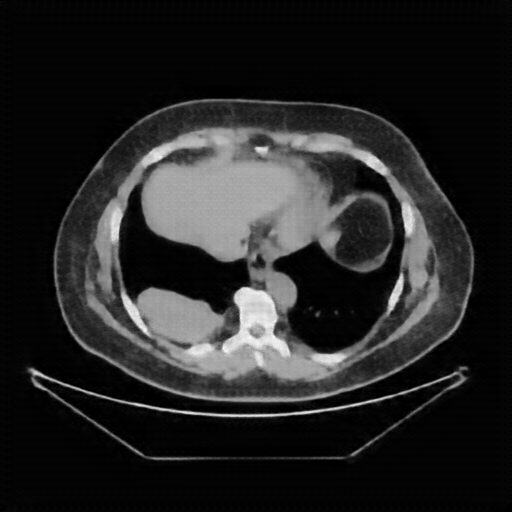

Original NATIVE CT scan (input)

Full window (WL 1023.5, WW 4095 β†’ Low βˆ’1024, High +3071)

Actual HU range: [-160.0, 240.0]

Lung window (WL -600, WW 1500 β†’ Low βˆ’1350, High +150)

Actual HU range: [-160.0, 150.0]

Mediastinum window (WL 40, WW 400 β†’ Low βˆ’160, High +240)